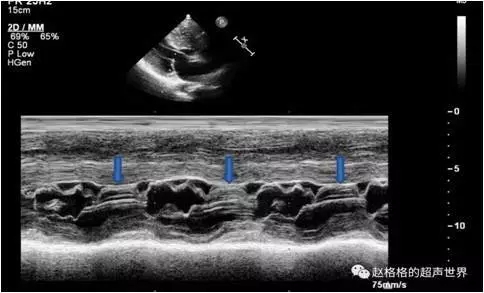

山东73岁的陈奶奶在10余年前开始出现胸闷、气短的症状,活动后胸背痛。近一年来症状加重,稍微活动后心前区闷痛、头痛、出冷汗,腰背部痛已经到了无法忍受的地步。在老家就诊时心电图显示心肌缺血,随即入院行冠脉造影检查却并未发现血管问题。却在术后心脏超声检查中发现,陈奶奶患有梗阻型肥厚性心肌病。 但是当地的医疗条件有限,无法解决心肌肥厚引起的不适。辗转找到了上海交通大学医学院附属第九人民医院心内科——张庆勇主任。 张主任发现,陈奶奶的症状是由于肥厚的心肌阻塞了左室流出道,导致使血液无法有效进入主动脉,于是没有足够的血液灌注于全身,同时供应心肌的血液也变少,导致心肌缺血。于是出现了典型心绞痛的一系列症状:气喘、心前区疼痛,呈闷痛,及腰背部痛。同样由于脑供血不足,也出现了脑供血不足的症状,如头部胀痛不适伴有黑朦等。但这种心脑血管缺血症状并非是由于血管本身的堵塞导致,而是由于血液灌注不足引起。 张庆勇主任团队对陈奶奶进行了心脏及全身的全面评估后,经过讨论认为可以借助一种新型的心脏内超声仪器(ICE)引导下经心内膜导管射频消融的微创手术,可以治疗陈奶奶的疾病。这个新型的治疗方法在于,不但可以利用心脏内血管超声(ICE)精准定位导管需要消融的部位,而且可以实时评估消融的效果,还有就是可以大大避免因消融引起的并发症,严重的传导阻滞而不得不行起搏器植入。2019年9月17日陈奶奶接收了这一新型的微创导管治疗方法,在手术过程中,陈奶奶即刻就感到胸闷减轻,10余年来从未有过的舒坦。术后恢复良好,第二日便下床自由活动,术后3天高高兴兴的出院回家了。术后3个月随访,陈奶奶表示术后的生活质量大幅提高,再也不会动不动就闷痛,也敢到处走走看看。 陈奶奶有这样的变化,在于导管消融解除了因心肌肥厚而梗阻的流出道,从而导致供血增加,症状改善: 手术前室间隔厚度为25.1mm,术后即刻缩减到21.0mm术后三个月随访室间隔厚度进一步缩减为18.0mm。 术前心室和主动脉之间的平均压力差达到了惊人的157mmHg,经过最狭窄处的流速为822cm/s。术后即刻平均压差降低到74mmHg,最狭窄处流速下降为590cm/s,术后三天更是进一步下降平均压差为41mmHg,最狭窄处流速为461cm/s。术后三个月平均压差为33mmHg,而最狭窄处流速为441cm/s,效果十分显著。 术后三个月心超 科普问题时间到 心脏血管没有问题, 为什么会有和心肌梗死一样的症状出现呢? 因为肥厚心肌的梗阻,使血液无法有效进入主动脉。没有足够的血液供应于全身的同时灌注心肌的血液也变少导致心肌缺血,于是出现了和心绞痛一样的症状:气喘、心前区闷痛,向左肩部放射,但这种心肌缺血并非是由于心脏血管堵塞造成,而是由于供血不足引起。严重的情况下,还可能出现一些心率失常,房颤以及恶性心律失常的表现,甚至猝死等。同时也会出现头晕、黑朦、晕厥等脑供血不足的表现,对患者的危害十分之大。 肥厚性心肌病到底是啥?怎么来的? 肥厚性心肌病(HCM)是以心肌肥厚为特征,心脏质量增加,可达正常心脏的2倍(约600g),甚至1000g以上。根据左心室流出道有无梗阻可分为梗阻性和非梗阻性肥厚型心肌病。 绝大部分肥厚性心肌病呈常染色体显性遗传,约60% 的成年患者可检测到明确的致病基因突变。 心脏的堰塞湖——肥厚梗阻型心肌病(HOCM) 肥厚梗阻型心肌病是HCM的一种特殊类型,约占该类疾病的1/4。 这类病人的心脏左室肥厚,在收缩期肥厚的室间隔使心室流出道狭窄。心室收缩时,肥厚的室间隔肌凸入心室腔,使血液容易淤积在左心房,就像在心脏中形成了堰塞湖一样,血液流不出去被围困在左房之中久而久之发生心房颤动、心绞痛、甚至猝死等。 得了HOCM会有什么样的症状呢? 患者症状表现为常反复发作劳力性呼吸困难、心区闷痛、晕厥等症状,生活质量差。患病后期可出现心脏扩张,演变为扩张性心肌病,同时还会引起房颤甚至于各种恶性心律失常出现,患者的不适症状日益加重。猝死与心力衰竭为主要的死亡原因。 起病多缓慢。约1/3有家族史。症状大多开始于30岁以前。男女同样罹患。 肥厚梗阻型心肌病的诊断 1.症状 (1)呼吸困难多在劳累后出现;(2)心前区痛多在劳累后出现,似心绞痛;(3)乏力、头晕与昏厥多在活动时发生;(4)心悸;(5)心力衰竭;(6)房颤。 2.辅助检查 1.胸部X线检查:心影增大,左心室增大,但无升主动脉扩大或瓣叶钙化征象。晚期病例则左心房、右心室亦可增大,肺野血管郁血。 2.心电图检查:显示左心室肥大和劳损,V3-V5导联特征性T波倒置,有时前胸aVL和I导联呈现异常Q波。 肥厚型心肌病心电图表现 3.心脏磁共振成像 心脏磁共振成像较超声心动图提供的信息更多。钆对比剂延迟强化 (1ate gadolinium enhancement,LGE)是识别心肌纤维化最有效的方法,LGE与死亡、SCD等风险正相关。约65%的HCM患者出现LGE,多表现为肥厚心肌内局灶性或斑片状强化,以室间隔与右心室游离壁交界处局灶状强化最为典型。 4.超声心动图检查 显示左心室壁显著增厚,心室间隔较心室后壁更为肥厚,左心室腔小,流出道狭窄和心脏收缩时二尖瓣前瓣叶向前移位(SAM征)。 超声心动图 SAM征小知识 究竟该如何治疗? 目前,梗阻性肥厚型心肌病(HOCM)的药物治疗有——β受体阻断药、维拉帕米等控制心率药物,但治疗效果有限。 同时还有几种特殊的方法来减轻心肌肥厚的问题。 外科室间隔心肌切除术 室间隔心肌切除术包括经典Morrow手术和目前临床应用较多的改良扩大Morrow手术。研究证实,HCM患者接受外科手术治疗后,远期生存率接近于正常人群。 但也有缺点:需要打开胸腔,切开心脏。手术只是解剖切除,无法评估对传导系统的影响,传导阻滞发生率较高。 经皮室间隔化学消融术(PTSMA) 是通过穿刺股动脉的方法将球囊导管送至肥厚心肌的供血血管(常为第一间隔支),在供血血管内缓慢注射一定量的无水酒精,导致肥厚心肌部分坏死,肥厚心肌变薄、收缩力减弱,流出道梗阻减轻,达到治疗目的。 该方法总体上安全有效,但缺点在于梗阻型心肌病的支配间隔的血管比较弥散,没有好的靶血管可供注入无水酒精,因此很难达到好的治疗效果。在解除左心室流出道压差(LVOTPG)的效果较差,如无水酒精漏入前降支或交通支开放导致无水酒精流向非靶目标区域,造成非靶目标心肌梗死。同时容易引起房室传导阻滞,需要安装心脏起搏器的可能性更大。 心肌内射频消融术 在影像技术引导下将特制诊疗装置经皮经心肌穿刺抵达心脏靶区诊断或治疗心脏疾病的新术式。该术式在超声指导下,经皮经肋间将射频消融穿刺针通过心尖置入肥厚的室间隔前壁(AIVS)进行消融,随后在室间隔后壁(PIVS)重复这一操作,对室间隔进行充分消融,进而解除左室流出道(LVOT)梗阻。Liwen术式治疗HOCM的机制在于通过高频电波导致肥厚的心肌组织细胞内的离子产生热效应,局部温度高达90-100℃,进而导致肥厚的心肌细胞脱水坏死,同时还可以达到阻断肥厚心肌组织血液供应的效果。 ICE辅助下心内膜导管射频消融微创介入术 局部麻醉之后,导丝从腹股沟处动脉和静脉进入。手术过程在心腔内超声(ICE)和三维心脏标测系统指导下,精确定位SAM室间隔接触区域进行消融,使得主动脉和心室内的压力阶差显著下降,血流快速的流入,类似于打开了堰塞湖的最狭窄处,从而增加了主动脉内的供血,使得全身缺血症状减轻并消失。 该项技术操作简便、精准、创伤小,并可以反复消融。最大优势是在操作过程中,能精准定位需要消融的部位,动态观察消融的效果,而且消融导管远端的双极电位描记,能避免对传导系统的附带损害,不易发生严重的传导阻滞。病人术后恢复快,一般第二天可以下床,三天就可以出院。是目前在治疗肥厚梗阻型心肌病中一种新型有效的方法。 四种术式的优缺点对比 外科室间隔心肌切除术 优点:患者接受外科手术治疗后,远期生存率接近于正常人群。 缺点:需要在深度麻醉下打开胸腔,切开心脏。手术只是解剖切除,无法评估对传导系统的影响,传导阻滞发生率较高。 经皮室间隔化学消融术(PTSMA) 优点:操作简便 缺点:若没有好的靶血管,则治疗效果差。易引起非靶目标心肌梗死以及房室传导阻滞。 心肌内射频消融术 优点:不容易损伤传导系统、引起传导组织的可能性小。 缺点:操作难度大、无法精准定位、没有专用的消融针。 经内膜导管射频消融 (RFCA) 优点:操作简便、精准、创伤小,并可以反复消融。最大优势是在操作过程中, 持续监测消融导管远端的双极电描记图,并避免了对传导系统的附带损害。RFCA 是安全有效的改善肥厚心肌并减轻症状的方法。 经内膜导管射频消融术是肥厚梗阻型心肌病治疗的一项新突破,该技术创伤小,精准性高,手术并发症小,治疗效果明确,是肥厚梗阻型心肌病患者的一大福音。目前由张庆勇主任率领的上海交通大学医学院附属第九人民医院心内科电生理团队已能成功的开展经内膜导管射频消融术。希望通过该项技术,能够造福更多的肥厚梗阻型心肌病患者。 延伸阅读